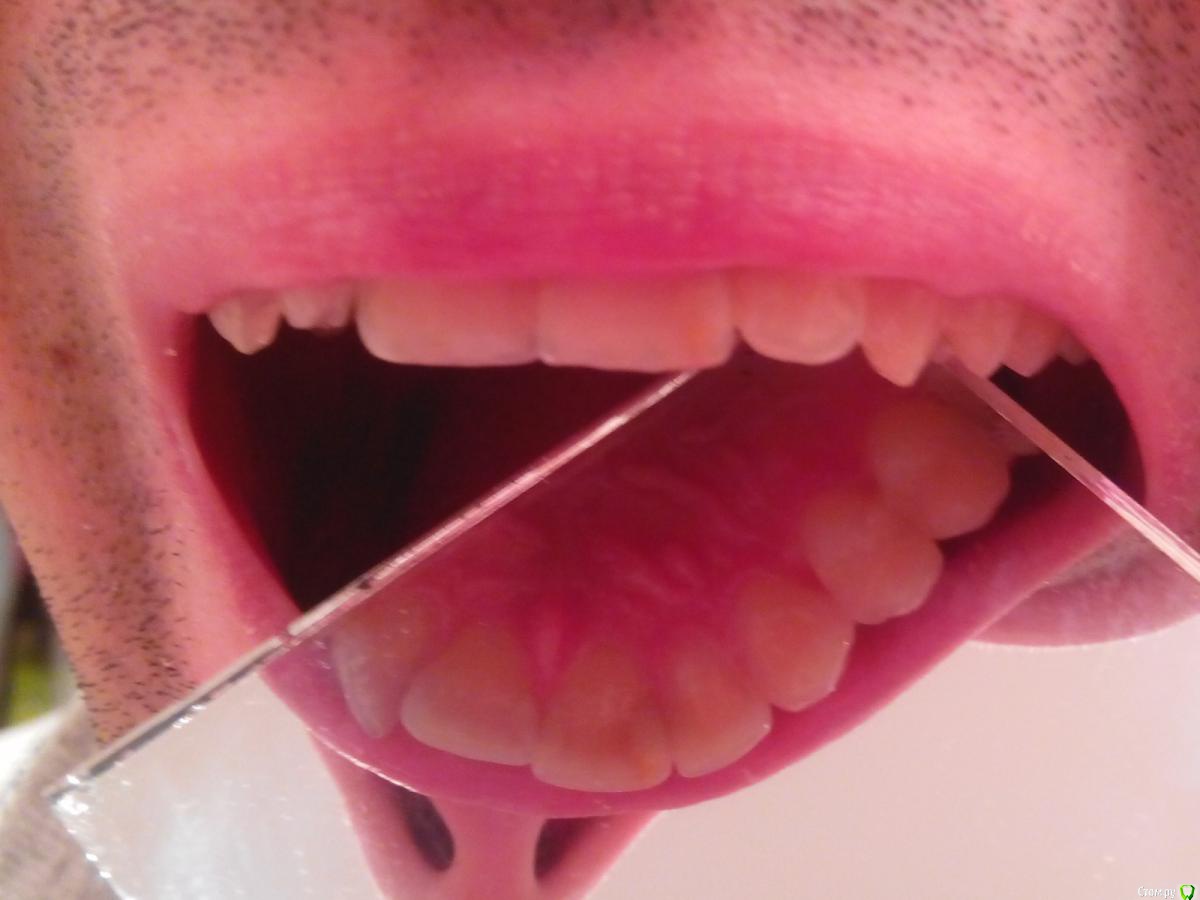

eizo Опубликовано 5 января, 2015 Поделиться Опубликовано 5 января, 2015 (изменено) Уважаемые специалисты и просто знатоки, помогите определиться по снимку на счёт наличия кариеса в 21м и/или 22м зубах. .Только что сделал снимок участка между 21м и 22м зубом (хотя снимок непонятный получился на мой взгляд).У меня уже 7 лет пломбав частив 21го зуба ближе к краю на границе с 22м. В середине ноября треснул 21й с нижней кромки, но болевых ощущений не было. Стоматолог в районнной ничего не смог предложить, ничего не обнаружил. Перед новым годом начали проявляться неприятные ощущения после приёма пищи, причём по собственным ощущениям именно на краю 22го со стороны примыкания к 21му.Сходил в другую клинику, терапевт сходу предположил рецидив кариеса в 21м, отвергая какие-либо дефекты в 22м.На снимке вроде бы ракурс с внутренней стороны челюсти (снимок производился с датчиком).Насколько я могу разобраться на 22м наблюдается дефект. А вот на счёт 21го -там где светлое пятно - это должна быть пломба. Изменено 5 января, 2015 пользователем eizo Ссылка на комментарий